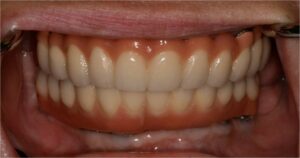

Η Προσθετικη οδοντιατρικη ειναι ο κλαδος της οδοντιατρικης που ασχολειται με την αποκατασταση μεγαλης η μικρης νωδοτητας στον οδοντικο φραγμο.

Η Προσθετικη Οδοντιατρικη χωριζεται σε

- Ακινητη προσθετικη, δηλαδη στεφανες και γεφυρες

- Κινητη προσθετικη, δηλαδη μερικες και ολικες οδοντοστοιχιες

- Προσθετικη επι εμφυτευματων